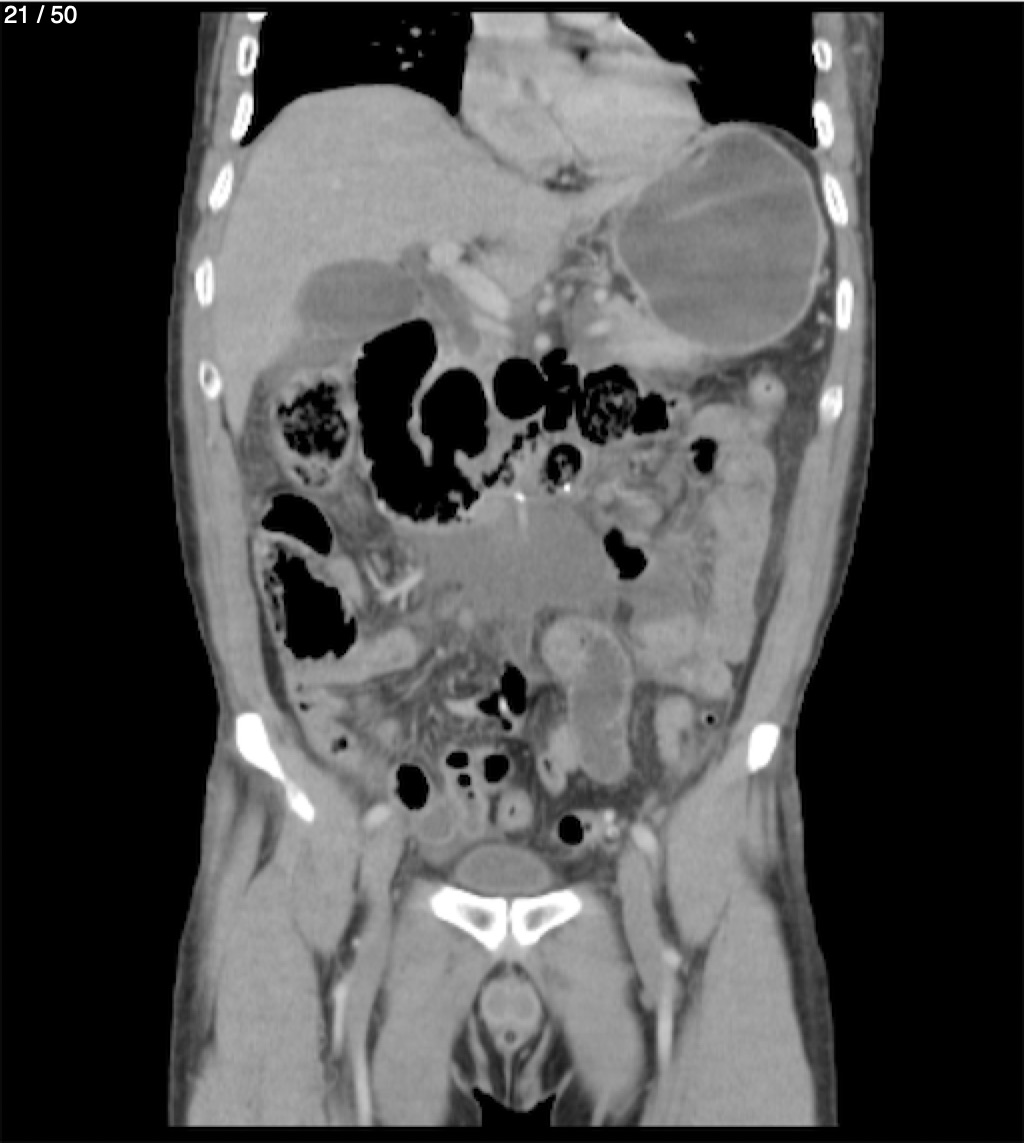

Alonso Victorio Ruiz 62A - T.C Abdomen Syc